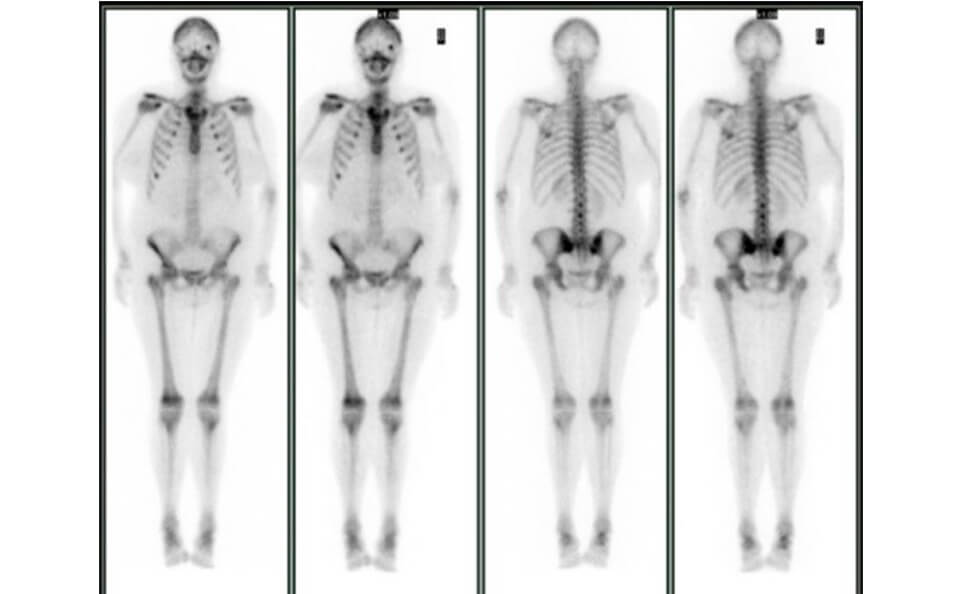

当センターでは、主に⾻シンチグラフィ、⼼筋(負荷・安静)シンチグラフィ、脳⾎流シンチグラフィの検査を⾏っています。そのほかにも、甲状腺シンチグラフィや腎動態シンチグラフィなど多種多様な検査の受け⼊れ態勢も整っています。

⾻シンチグラフィ

⾻シンチグラフィ